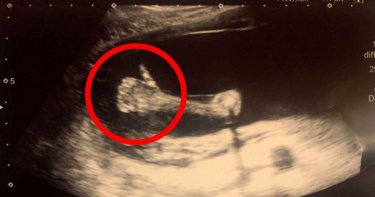

真的豎起大拇指!5個月胎兒大力「比讚」 護士驚呆:從未見過

超音波在孕期中扮演著相當重要的角色,醫師能藉此觀察胎兒的生長狀況,準媽媽也能窺探小寶貝的模樣,英國林肯郡一名孕婦,近日前往醫院進行產檢時,竟從超音波畫面看見腹中的寶寶比出「讚」的手勢,讓經驗豐富的助產護士不禁驚呼連連,引發一陣熱烈討論。綜合外媒報導,去年12月9日,33歲的荷莉(HollyGiles)懷胎剛滿20週,閨蜜陪她到朝聖者醫院(Pilgrim Hospital)接受產檢,她躺上床不久後,醫護人員馬上說了句「我的天啊!」荷莉隨後將視線移往螢幕一看,竟發現寶寶豎起了大拇指,這個可愛的驚喜讓眾人頻頻讚嘆。經驗豐富助產護士表示,從沒見過這個情況,且胎兒在子宮不斷扭動,卻始終保持著「讚」的手勢,持續了好一陣子。荷莉被這可愛的舉動萌翻,認為是孩子在告訴自己「一切都會沒事」,荷莉在16歲那年遭逢喪母之痛,她認為這個孩子是「媽媽送來的禮物」,已經迫不及待迎接寶寶到來。